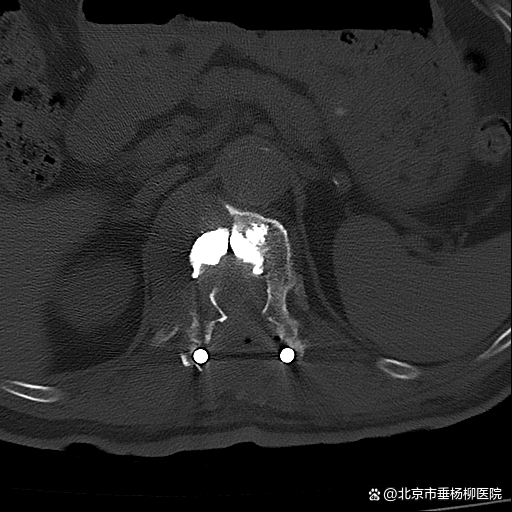

原来在一年前,黄老因罹患肾脏肿瘤行左肾切除术,但术后病理不详。脊柱外科(骨四科)主任姜树东在得知这一情况后,立即为患者完善胸腰椎核磁共振检查。结果提示T12椎体骨质破坏,结构不完整,向后压迫硬膜囊,椎管狭窄,脊髓受压;周围软组织肿胀;考虑病理性骨折(T12),脊柱转移瘤可能性大。随后,再行T12椎体穿刺活检术。同时患者家属提供了患者的既往病历:左肾肿瘤符合透明细胞癌。

椎骨活检病理结果显示:(T12椎体内组织)送检少许破碎骨组织、多量纤维结缔组织及纤维素渗出坏死组织。纤维结缔组织部分间质疏松水肿,部分区域细胞密集,局灶可见透明细胞浸润。结合病史及免疫组化结果,符合肾透明细胞癌转移。